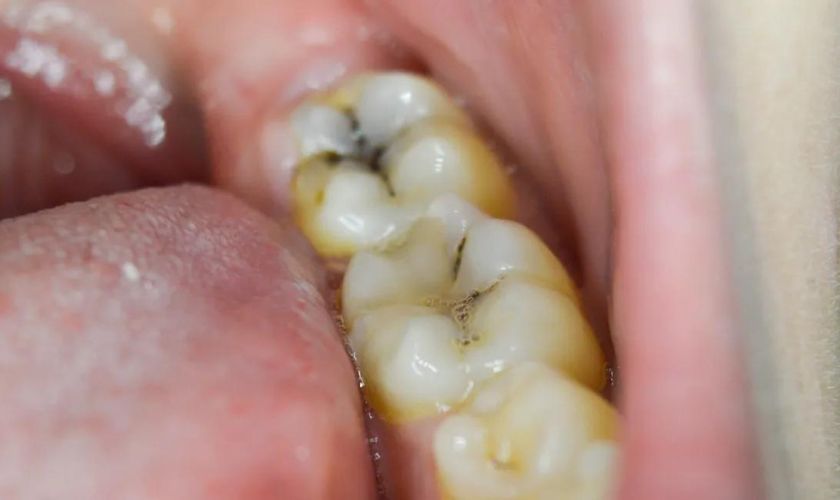

Cavities, also called dental caries, are areas of permanent damage in the hard surface of your tooth. They form when bacteria in your mouth feed on sugars from food and drinks, producing acids that erode the enamel.

Once enamel loses minerals faster than it can repair itself, decay begins. If this process continues, a visible hole forms, and at that point, professional dental treatment is necessary.

Once a cavity has formed, no amount of brushing, rinsing, or home remedies can reverse it. The enamel doesn’t regenerate, meaning the hole remains and will only get larger over time. If ignored, the decay can spread into deeper layers of your tooth, causing pain, infection, or even the need for a root canal.

If you experience tooth sensitivity, pain while chewing, or notice dark spots or small holes, schedule a dental exam right away. Early detection can mean the difference between a simple fluoride treatment and a filling—or worse, a root canal.